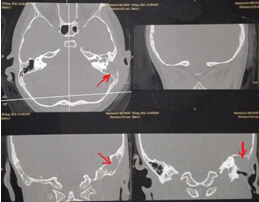

該患兒既往無中耳炎及耳流膿病史,僅表現(xiàn)為1個月前耳后稍有紅腫、疼痛,在當(dāng)?shù)蒯t(yī)院曾被診斷為“蚊蟲咬傷”所致,家長也未引起足夠的重視。近半月來,患兒耳后紅腫疼痛加重,遂到我市某三甲醫(yī)院就診,行高分辨率中耳乳突CT,發(fā)現(xiàn)側(cè)顱底、中耳乳突腔巨大新生物占位,乳突骨皮質(zhì)破壞吸收,并可疑耳后骨膜下膿腫形成。病情若進(jìn)一步發(fā)展,膽脂瘤破壞顱底骨質(zhì),將極有可能并發(fā)腦膜炎、腦膿腫,甚至出現(xiàn)敗血癥、腦疝等,危及生命。

1.術(shù)前耳后紅腫 2.術(shù)前CT1

3.術(shù)前CT2 4.術(shù)中術(shù)腔中的巨大膽脂瘤